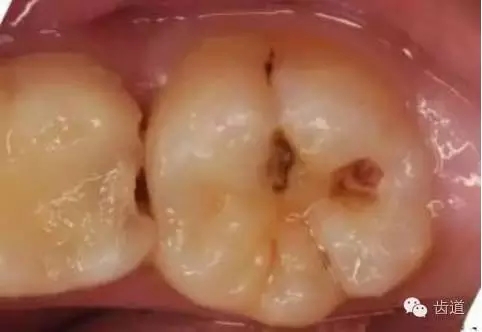

2、中齲:牙本質(zhì)淺層齲。

2.webp.jpg